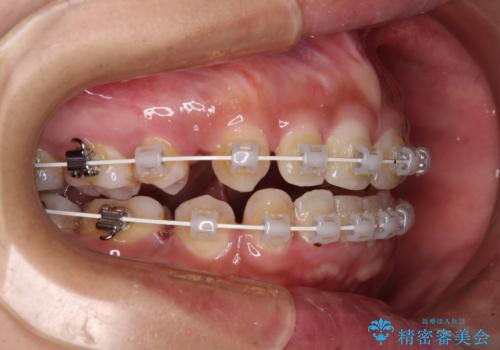

- 矯正装置

- 審美装置

- 治療計画

- 口元の突出感と上下前歯のズレを気にして来院された患者様です。

舌の突出癖により上下の前歯は非接触であり、更には奥歯の咬み合わせが非対称となっている状態でした。

舌のトレーニングを行わないと上下前歯の接触達成は困難であるため、トレーニングをしっかりと行っていただきながら、治療を進めて行くこととしました。

通常は上下左右の第一小臼歯4本を抜歯することになりますが、右側臼歯部の咬合が上顎前突気味であったため、下顎右側のみ第二小臼歯を抜歯し、ワイヤー装置にて矯正治療を行うこととしました。